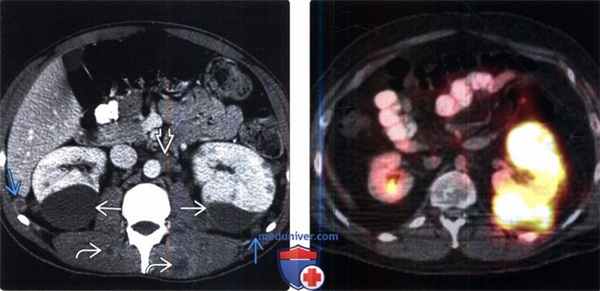

(Слева) КТ с контрастированием, аксиальная проекция: визуализирован двусторонний гидронефроз вследствие слившихся узловых метастазов забрюшинного пространства, ставших причиной мочеточниковой обструкции.

(Справа) КТ с контрастированием, аксиальная проекция: слившиеся узлы, окружающие чревный ствол, вследствие метастазирования рака пищевода. Рак дистального отдела пищевода часто метастазирует в верхние лимфатические узлы брюшной полости, печень или легкие.

(Слева) КТ с контрастированием, аксиальная проекция: у мужчины 21 года вследствие метастатической меланомы выявлены двусторонняя субкапсулярная гематома почки, паранефральные узелки мягкой ткани, забрюшинная лимфаденопатия и поражение мышц.

(Справа) В левой почке и околопочечном пространстве выявлена ФДГ-положительная опухоль, представляющая собой гематогенные метастазы меланомы в забрюшинное пространство. ПЭТ/КТ—идеальный метод визуализации ФДГ -положительных опухолей, так как часто позволяет обнаружить метастазы скрытых локализаций и в лимфатических узлах нормальных размеров.